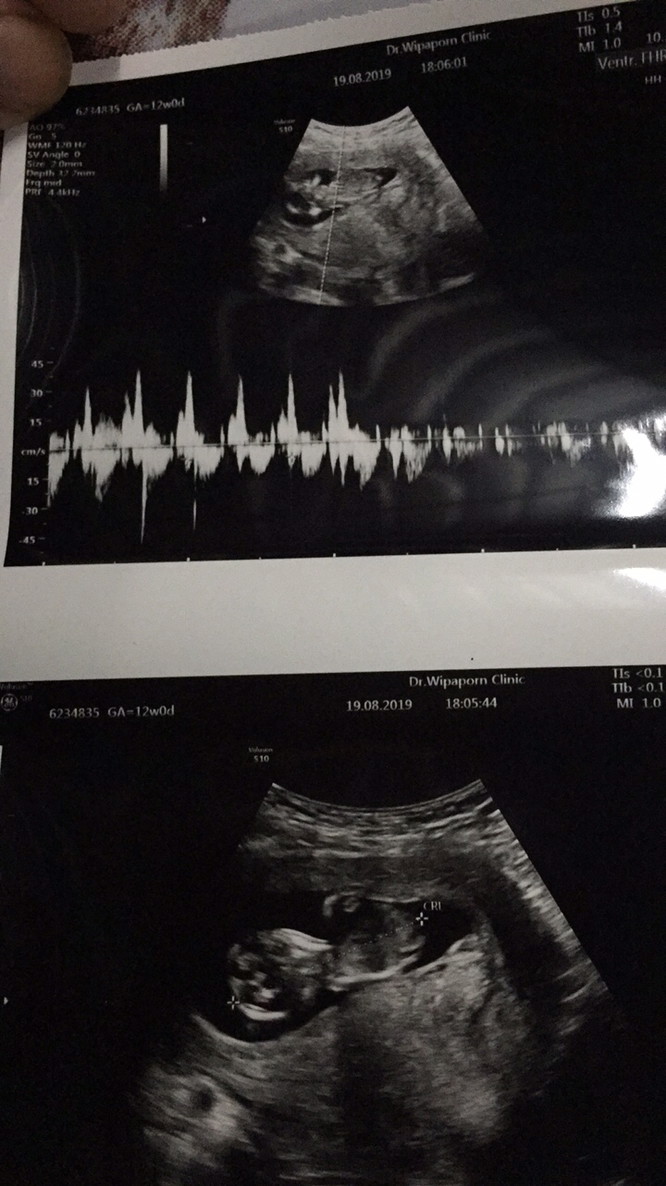

8มีนาค่ะ หมอบอกอาจจะคลาดเคลื่อน...แต่หมอยังไม่ซาวให้เลย เขานัดซาว อีก2เดือนน่าค่ะ. ตอนนี้ท้อง3เดือนแล้ว 💛🧡💛